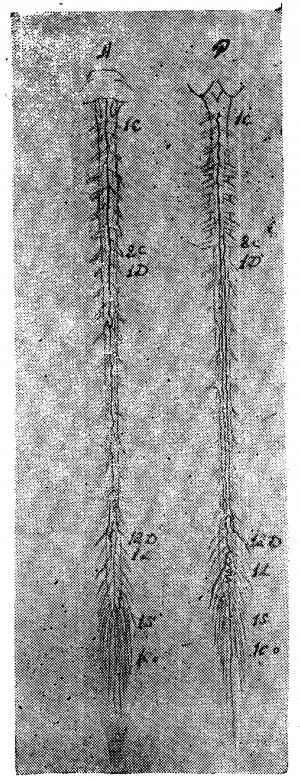

Внепозвонковые вены образуют по задней поверхности позвоночника очень сложное сплетение, в которое, помимо вен спинного мозга, вливается ещё множество вен из спинной мускулатуры. От этого сплетения, покрывающего широкими, неправильными петлями дуги позвоночника, отходят анастомозы к заднему внутреннему сплетению, проникая в полость позвоночника через жёлтую связку. Большая часть оттоков заднего внепозвоночного сплетения направляется вдоль поперечных отростков позвонков, проходит между отростками и впадает в межреберные вены или же (в Шейной области), сливаясь в один ствол, образует позвоночную вену, во всех отношениях аналогичную одноимённой артерии. На передней поверхности позвоночника описывается несколько внепозвоночных вен, исходящих из позвонков и связок позвоночника; эти слаборазвитые стволики впадают в соседние стволы, главным образом, в непарную вену (рис. 4, 5).

Форма первая. Рис. 6, 7, 8 дают примеры первого типа.

На передней поверхности препарата, изображенного на рис. 6, можно отметить неравномерность калибра среднего ствола, склонность к образованию островков, но, в общем, тракт можно довольно легко проследить на всём его протяжении. На рис. 7 задержка редукции выражена больше: калибр переднего тракта очень мелок, тракт почти прерывается, отклоняясь несколько в сторону; боковые же тракты выражены относительно лучше. Гораздо больше выражена задержка редукции на препарате, изображённом на рис. 8. В нижней части шейного отдела и в грудном отделе средний тракт только отгадывается в системе продольных петель, с частыми боковыми оттоками (ср. верхнюю грудную область, особенно 3-й грудной сегмент, где средний тракт совершенно отходит в сторону, прерывается и оба его отрезка впадают отдельно в параллельные венозные стволики третьего грудного корешка). В области 12-го грудного—1-го поясничного сегмента тракт также отклоняется в сторону, образует островок и почти истощается. В грудной области тракт распадается на два слабых извилистых рукава, образующих длинный островок, а в области 8—11-го сегмента видны даже три параллельных стволика. Оттоки рассеяны, мелки, на одном корешке зачастую видны 2—3 венки. Вена Адамкевича выражена слабо (1 крестцовый корешок слева); боковые тракты едва намечаются прерывистой линией. Эту картину можно считать типичной задержкой редукции, наиболее выраженной для передней венозной сети в ряду изученных нами препаратов.

На рис. 9 видна неравномерность калибра переднего тракта, его извитость, рассеянность оттоков; на рис. 10 видны те же черты: тракт прерывается, извит, образует островки, во многих местах существуют довольно значительные параллельные стволы. Этот рисунок заслуживает внимания: на изображённом здесь препарате задержка редукции выражена и спереди и сзади, а вместе с тем венозные стволы поверхностной сети широки, налиты кровью и при невнимательном взгляде препарат легко отнести к магистральному типу, что было бы, конечно, ошибочно. Развитость стволов, набухлость вен в данном случае являются следствием возрастного изменения и нарушения венозного кровообращения у сердечнобольного (см. ниже гл. IV, болезни сердца).

Задняя поверхность препаратов, изображённых на рис. 6, 7, 8, 10, 11 представляет ещё более резкую картину задержки редукции первичной венозной сети. Так, на рис. 10, несмотря на резкую набухлость вен, в шейной и верхней грудной области почти не выражены продольные стволы: это еще ясней видно на рис. 11, где местами продольные стволы совсем не видны, местами же они только намечаются. Изображённый на рисунке препарат представляет большой интерес с патологической точки зрения и к нему мы вернёмся в гл. IV.

Очень типична картина задержки редукции первичной венозной сети задней поверхности, видная на рис. 7. Мы отмечаем резкую неравномерность калибра и плохое развитие среднего тракта, отклонение от средней линии, перерыв на уровне 7-го — 11-го грудного сегмента, плохую выраженность продольных стволов, местами трудно выделяемых из венозной сети, рассеянность оттоков. Аналогичная картина видна и на рис. 8.

Вторая форма. Магистральный тип поверхностных вен спинного мозга характеризуется двумя основными чертами: хорошей выраженностью среднего тракта и хорошей централизацией оттоков. Боковые продольные тракты обычно только намечаются и, повидимому, вообще редуцируются (рис. 12, 13, 14).

На рис. 12 довольно хорошо выражен магистральный тип вен передней поверхности, строение же вен задней поверхности является переходным. Лучше магистральный тип выражен на обеих поверхностях препарата, изображённого на рис. 13, где почти не видны боковые тракты, а средние тракты представляются хорошо развитыми, относительно равномерными по калибру, оттоки хорошо централизованы. На рис. 14, 15, 16, 17 и 18 можно видеть различные переходные вариации.